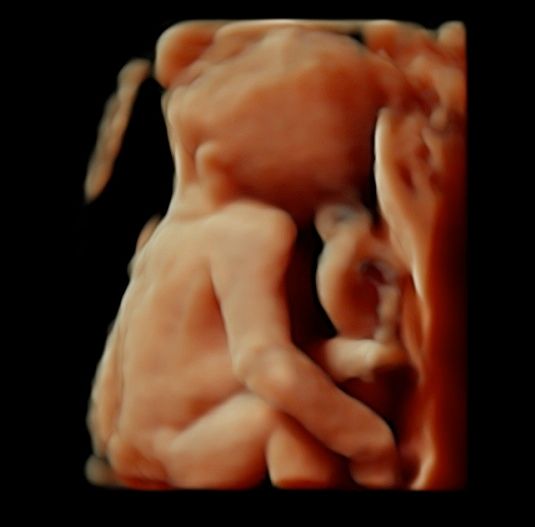

Foto e video

• Ecografia morfologica